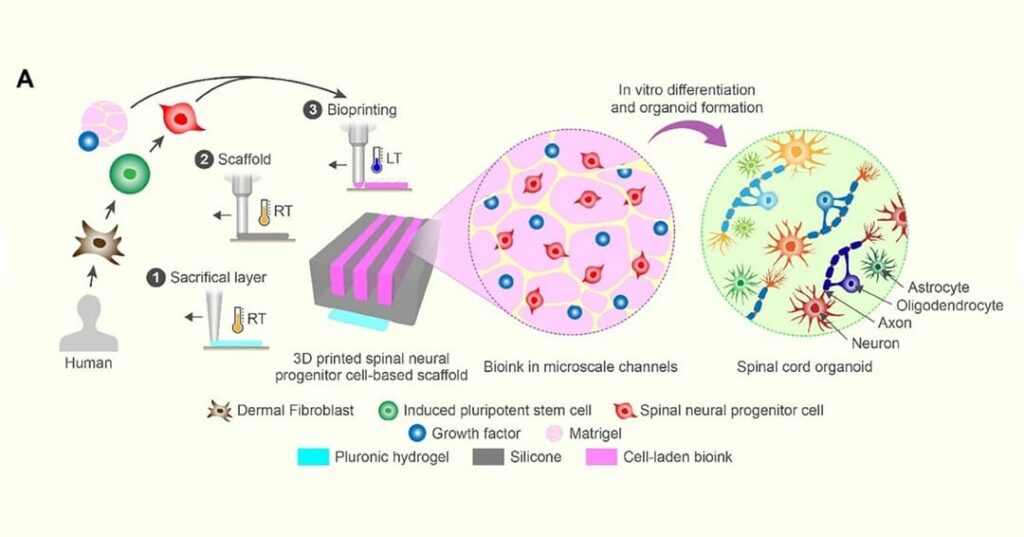

Este equipo desarrolló un método innovador que integra impresión 3D, biología de células madre y tejidos cultivados en laboratorio para favorecer la reparación de este tipo de lesiones.

El equipo desarrolló una estructura innovadora impresa en 3D para órganos cultivados en laboratorio, llamada andamio organoidal, que contiene canales microscópicos.

Estos canales se llenan con células progenitoras neurales espinales derivadas de células madre adultas humanas, capaces de dividirse y diferenciarse en tipos específicos de células maduras.

“Utilizamos los canales impresos en 3D de la estructura para dirigir el crecimiento de las células madre, lo que garantiza que las nuevas fibras nerviosas crezcan de la forma deseada. Este método crea un sistema de relevo que, al colocarse en la médula espinal, evita el área dañada”.